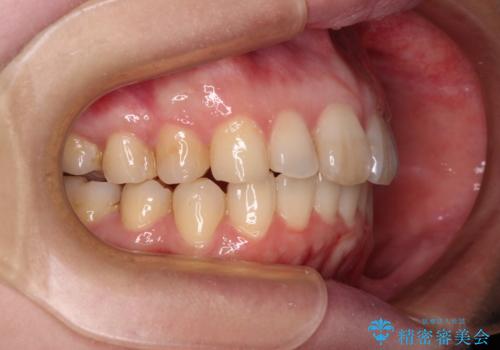

- 上顎前歯の突出感と、前歯のクロスバイトを気にして来院された患者様です。

前歯の叢生と口元の閉じにくさを気にして来院された患者様です。

奥歯の咬み合わせを見ると、上顎が下顎に対して相対的に前方にありました。

カリエール・ディスタライザーを用いたことで上顎前歯の突出感はスムーズに解消され、歯列不正は1年半ほどでほぼ改善することができました。